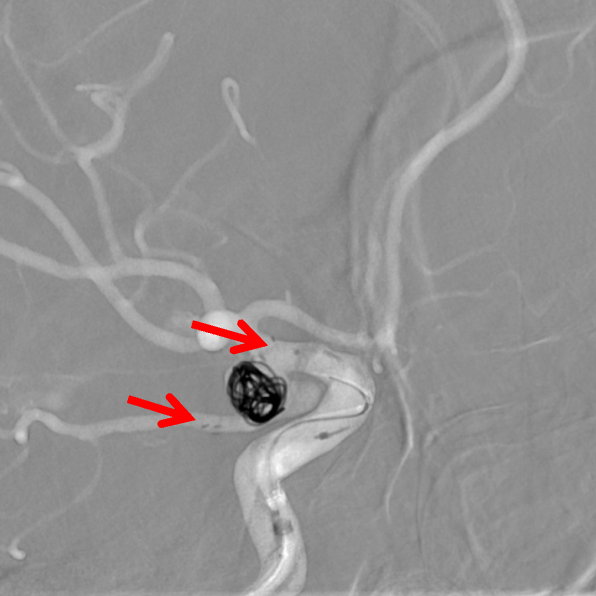

左侧颈动脉正侧位造影:左侧颈内动脉后交通段动脉瘤(箭头所示)。

左侧颈内动脉3D造影可见动脉瘤位于后交通动脉起始处。

3D血管造影可见左侧后交通动脉瘤,大小约7.05×7.47mm,瘤颈3.68mm,考虑胚胎型大脑后动脉。

栓塞微导管到位后首先使用弹簧圈栓塞,成篮不稳定,使用Atlas支架4.0mm×21mm保护后交通动脉(箭头所示支架头端及尾端),释放支架的要点在于精准定位,同时判断微导管张力,在预设的释放起点准确打开支架,之后顺行释放支架,支架的尾端打开时须不受颈内动脉管径约束,依靠张力摆动至颈内动脉后交通动脉段远端,起到保护后交通动脉的目的。